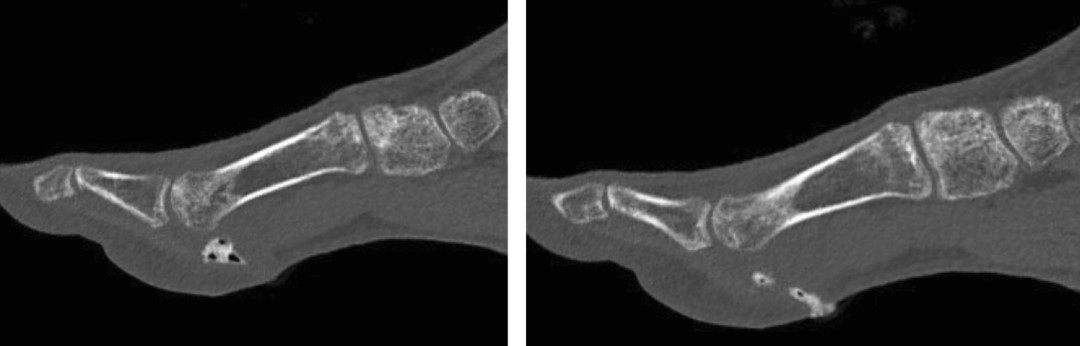

At five weeks from the onset of symptoms, the patient returned to the clinic with spontaneous fistulization of the hallux, accompanied by purulent drainage. Examination revealed erythema and redness in the area, with decreased swelling, and a fistulous tract on the medial and plantar aspect of the hallux actively discharging purulent material. Suspecting SA, a specimen for culture was taken, and the patient was admitted for further evaluation by fistulography. The fistulogram revealed a 1-2 cm fistulous tract extending from the plantar, medial, and proximal aspects of the hallux towards the medial sesamoid, without communication to the lateral sesamoid or other structures; small quantities of air in the form of bubbles were also found within the fistulous tract (Figure 2).

Figure 2